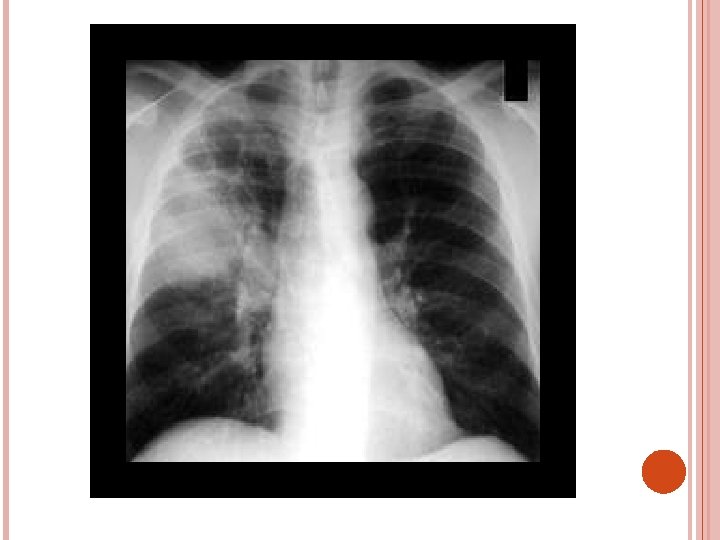

PNEUMOCYSTITIS JIROVECI Fungal infection pulmonary diffuse bilateral alveolar pattern of infiltration. in wide spread infection lungs are massively consolidated fever , tachycardia , tachypnea , hypoxemia , non productive cough TMP – SMZ , dapsone to those intolerant to bacterim , aerosolized pentamident , primaquine , clindamycin

DIAGNOSTIC STUDIES History collection , physical examination Chest X-Ray lab Microbiology serology ABG

PLEURAL EFFUSION Collection of fluid in a pleural space , rarely a primary disease , usually secondary to other disease It is a sign of serious disease Normally it contains 5 – 15 ml